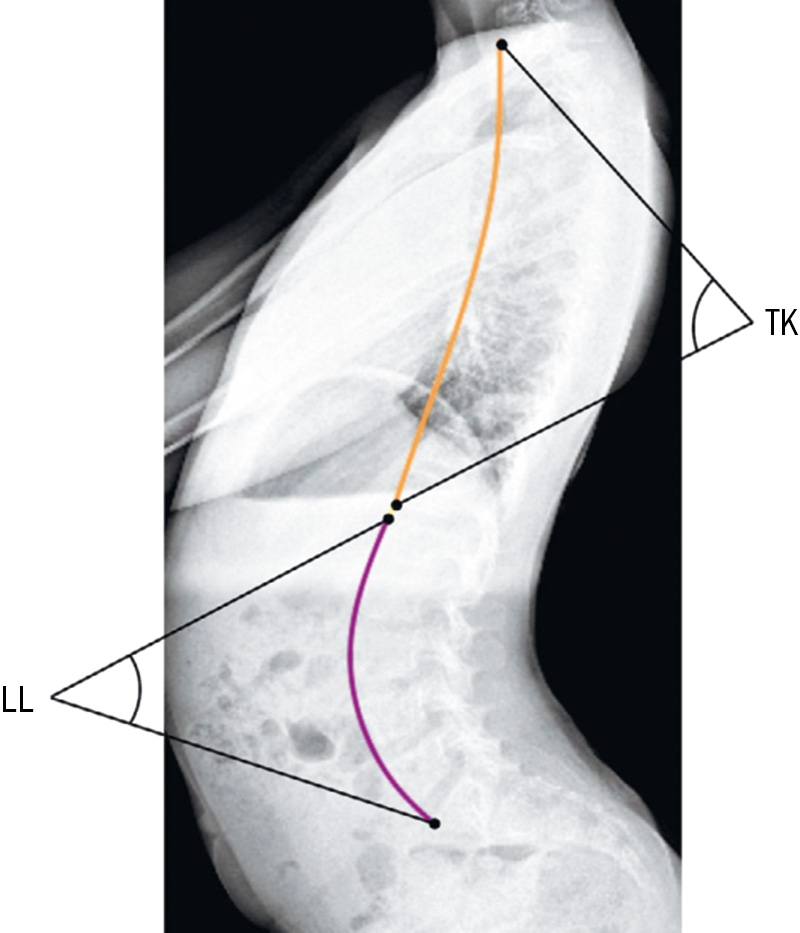

Оценка включала следующие показатели: Pelvic tilt (PT), Sacral slope (SS), Pelvic incidence (PI), Lumbar lordosis (LL), Thoracic kyphosis (TK), Sagittal vertical axis (SVA) (рис. 1 и 2). Эти параметры отражают позвоночно-тазовые соотношения, изменение которых позволяет оценить влияние хирургической коррекции СККС на сагиттальный баланс у пациентов с ДЦП.

Рис. 1. Схематическое изображение ключевых угловых показателей таза, определяемых по стандартной боковой рентгенограмме. PI, Pelvic incidence — угол между перпендикуляром к верхней замыкательной пластинке SI и линией, идущей к центру головки бедренной кости; PT, Pelvic tilt — угол между вертикалью и линией, соединяющей центр верхней пластинки SI с центром головки бедра; SS, Sacral slope — угол между горизонталью и верхней замыкательной пластинкой SI.

Рис. 2. Схема измерения сагиттальных параметров позвоночника по боковой рентгенограмме. TK, Thoracic kyphosis и LL, Lumbar lordosis определяют по углам между точками, соответствующими границам и вершинам дуг грудного и поясничного отделов позвоночника.

При оценке сагиттальных параметров позвоночника и таза выявлено статистически значимое увеличение поясничного лордоза (LL) с 39,2±6,3° до 45,8±5,9° (p=0,018). Остальные показатели глобального сагиттального профиля (PI, PT, SS, TK и SVA) значимых изменений не продемонстрировали (p >0,05, рис. 1).